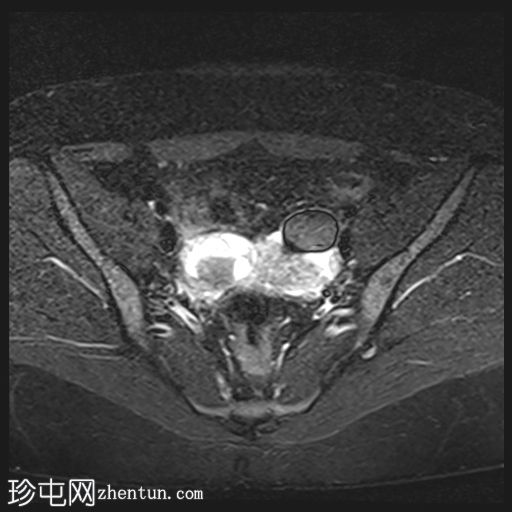

轴位

T2加权像

双侧卵巢位置接近(卵巢相吻),左侧卵巢内可见一边界清晰的囊性病变,大小约3.1 × 2.7 × 2.9 cm,T1加权像呈高信号,T2加权像可见暗点征及内部暗点征。以上MRI特征符合卵巢子宫内膜异位囊肿的诊断。

右侧卵巢可见一囊肿,大小约为 2.8 × 2.0 × 2.2 cm,T1 加权像呈高信号,囊内可见液-液平面,提示囊内含有不同时期的出血性物质。由于对侧卵巢存在典型的子宫内膜异位囊肿,且该囊肿无强化,影像学表现强烈提示为另一子宫内膜异位囊肿。

双侧卵巢均可见多个小卵泡。

双侧卵巢囊性病变,MRI 表现符合子宫内膜异位囊肿的特征,左侧较大。未见强化壁结节或实性成分,提示无恶性转化。